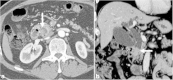

Malignancies of the biliary tract include cholangiocarcinoma, gallbladder cancers and carcinoma of the ampulla of Vater. Biliary tract adenocarcinomas are the second most common primary hepatobiliary cancer. Due to their slow growing nature, non-specific and late symptomatology, these malignancies are often diagnosed in advanced stages with poor prognosis. Apart from incidental discovery of gall bladder carcinoma upon cholecystectomy, early stage biliary tract cancers are now detected with computed tomography (CT) and magnetic resonance imaging (MRI) with magnetic resonance cholangiopancreatography (MRCP). Accurate characterization and staging of these indolent cancers will determine outcome as majority of the patients' are inoperable at the time of presentation. Ultrasound is useful for initial evaluation of the biliary tract and gallbladder masses and in determining the next suitable modality for further evaluation. Multimodality imaging plays an integral role in the management of the biliary tract malignancies. The imaging techniques most useful are MRI with MRCP, endoscopic retrograde cholangiopancreatography (ERCP), endoscopic ultrasound (EUS) and positron emission tomography (PET). In this review we will discuss epidemiology and the role of imaging in detection, characterization and management of the biliary tract malignancies under the three broad categories of cholangiocarcinomas (intra- and extrahepatic), gallbladder cancers and ampullary carcinomas.